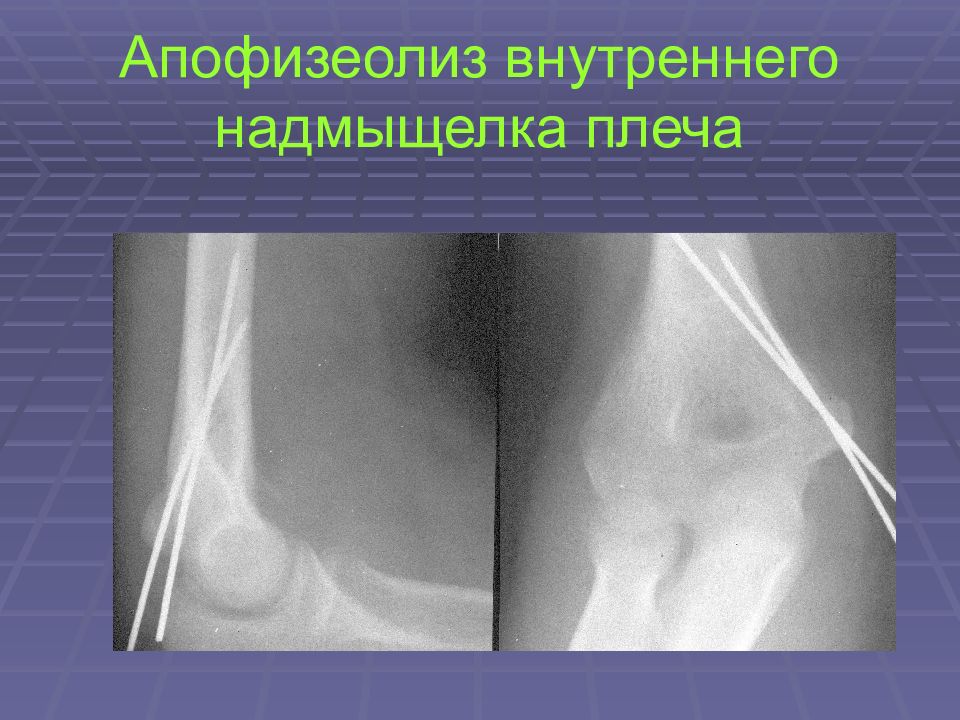

Слайд 26: Апофизеолиз внутреннего надмыщелка плеча

Слайд 27: Апофизеолиз внутреннего надмыщелка плеча

Слайд 28: Апофизеолиз внутреннего надмыщелка плеча

Слайд 29: Апофизеолиз внутреннего надмыщелка плеча